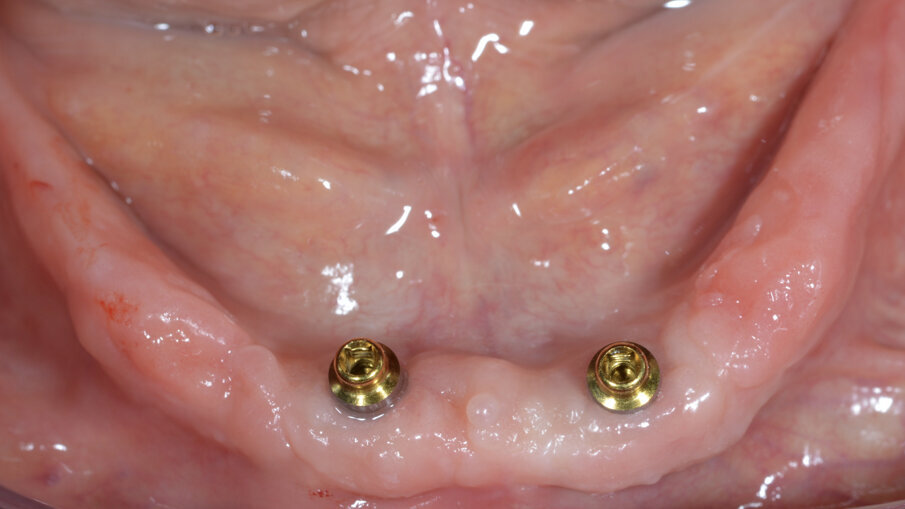

Varie analisi cliniche condotte hanno permesso di concludere che ad oggi il trattamento professionale di queste protesi debba essere eseguito in prima fase da una motivazione all’igiene orale. Questa fase d’istruzione alla corretta igiene implanto-protesica è un primo step fondamentale dove ci soffermeremo nel far conoscere il cavo orale e il tipo di riabilitazione al paziente. Passaggi già effettuati durante la fase di trattamento ma che necessitano di un riepilogo per rendere più consapevole della complessità del lavoro eseguito anche il paziente meno ricettivo. Ovvio che in fase di anamnesi si è già effettuata una scelta importante, capire se il paziente è capace di tenere una bocca in ordine. Se così non fosse bisogna orientare le proprie scelte terapeutiche su soluzioni implanto-protesiche più semplici da realizzare e da mantenere pulite come per esempio, nell’arcata inferiore, l’overdenture impianto-ritenuta e tessuto supportata con OT Equator (Rhein83, Italia) che è una tipologia di trattamento ad alta resa funzionale e migliorativa della qualità di vita e allo stesso tempo semplicissima da tener pulita (Fig. 4). I depositi di placca sul TiN titanio nitrurato ad alta resistenza, sono semplici da rimuovere sia a livello domiciliare che a livello professionale. Per la protesi fissa nella fase di consegna del manufatto protesico daremo delle prime istruzioni di igiene. Queste norme di igiene domiciliare saranno rinforzate con rilevatori di placca tritonale nelle sedute successive che ci aiuterà a far notare le zone che il paziente trascura ma soprattutto ci guiderà durante la rimozione del biofilm batterico.

Fig. 4_Overdenture mandibolare. Soluzione pratica e affidabile in pazienti con scarsa igiene orale.

Mostriamo di seguito l’esecuzione di un lavoro di protesi ibrida su impianti tipo Toronto su sistematica OT Bridge (Rhein83, Italia). Il paziente, edentulo con più di 80 anni di età viene operato in chirurgia guidata (Figg. 11, 12). Vengono inseriti 4 impianti TSIII (Osstem, Korea) del diametro di 4 x 8.5 in zona 16, 3.5 x 11.5 in zona 12, 3.5 x 11.5 in zona 23 e 4 x 8.5 in zona 27. La progettazione è avvenuta con il software RealGuide (3Diemme, Italia) sfruttando le informazioni del montaggio dei denti della protesi totale. Nonostante la progettazione accurata, gli impianti non si sono potuti collocare in perfetto parallelismo per le condizioni ossee scarse. Quindi tra le varie fixture sono presenti disparallelismi, proprio per questo abbiamo deciso di utilizzare la sistematica OT Bridge (Rhein83, Italia) che risulta particolarmente vincente in caso di parallelismo tra i monconi. Abbiamo inserito gli abutment OT Equator (Rhein83, Italia) già al tempo della chirurgia e li abbiamo ricoperti con le viti di guarigione scegliendo la chirurgia one-stage (Figg. 13, 14).

Fig. 13_OT Equator inseriti al tempo della chirurgia.

Fig. 14_Healing abutment per chirurgia one-stage.